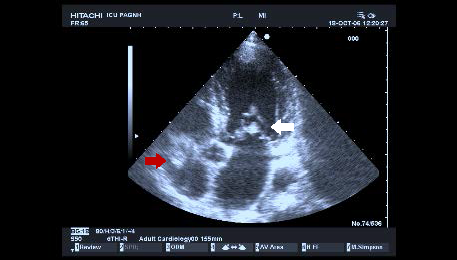

Εικ. 1. Κοιλιακή

λήψη μέσω κρανιεκτομής. Απεικονίζονται η μέση γραμμή και οι πλάγιες κοιλίες

(βέλος). 2. Οπτικό